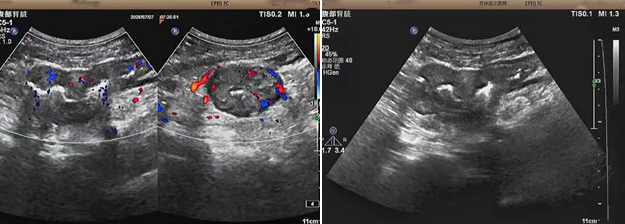

超聲檢查的結(jié)果進(jìn)一步揭示了病情的細(xì)節(jié):下腹部偏左腸壁顯著增厚,原本清晰的層次結(jié)構(gòu)遭到破壞,周圍脂肪間隙變得模糊,網(wǎng)膜回聲也出現(xiàn)增強(qiáng)的現(xiàn)象;同時(shí),腸腔狹窄的情況也得到了確認(rèn)。經(jīng)過完善的檢查,最終將病變精準(zhǔn)定位在乙狀結(jié)腸 - 直腸交界區(qū),并且對(duì)病變范圍及周圍浸潤情況做出了評(píng)估,這些關(guān)鍵信息為后續(xù)的診療工作提供了重要依據(jù),讓醫(yī)生們能更有針對(duì)性地制定治療方案。

我院超聲檢查在此次診療過程中展現(xiàn)出了顯著的技術(shù)亮點(diǎn)。一方面,它能做到 “明察秋毫”,通過高頻探頭可以清晰地顯示腸壁各層結(jié)構(gòu)的變化,為臨床判斷病變性質(zhì)提供了客觀、準(zhǔn)確的依據(jù),讓醫(yī)生能更清晰地了解腸道內(nèi)部的病變狀態(tài),另一方面,它實(shí)現(xiàn)了 “精準(zhǔn)評(píng)估”,不僅準(zhǔn)確找到了病變的位置,還能全面評(píng)估病變對(duì)周圍組織的影響,這對(duì)于協(xié)助醫(yī)生制定科學(xué)合理的治療方案起到了至關(guān)重要的作用,有助于提高治療的有效性和安全性。